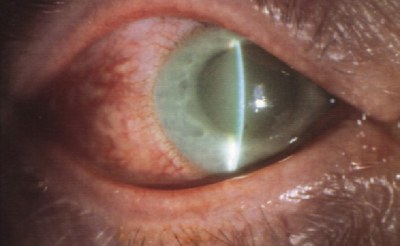

Αυτός ο τύπος γλαυκώματος είναι συχνότερος στους ασιάτες. Η ενδοφθάλμια πίεση αυξάνει ξαφνικά (οξύ γλαύκωμα) και προκαλεί έντονο πόνο στην περιοχή του ματιού που συνοδεύεται από έγχρωμους κύκλους γύρω από τα φώτα, θάμπωμα στην όραση και κόκκινο μάτι. Είναι επείγουσα κατάσταση που απαιτεί άμεση αντιμετώπιση.

Μπορεί να είναι είτε ανοιχτής είτε κλειστής γωνίας. Οφείλεται στην ύπαρξη άλλης τοπικής ή συστηματικής αιτίας που προκαλεί αύξηση της ενδοφθάλμια πίεσης.